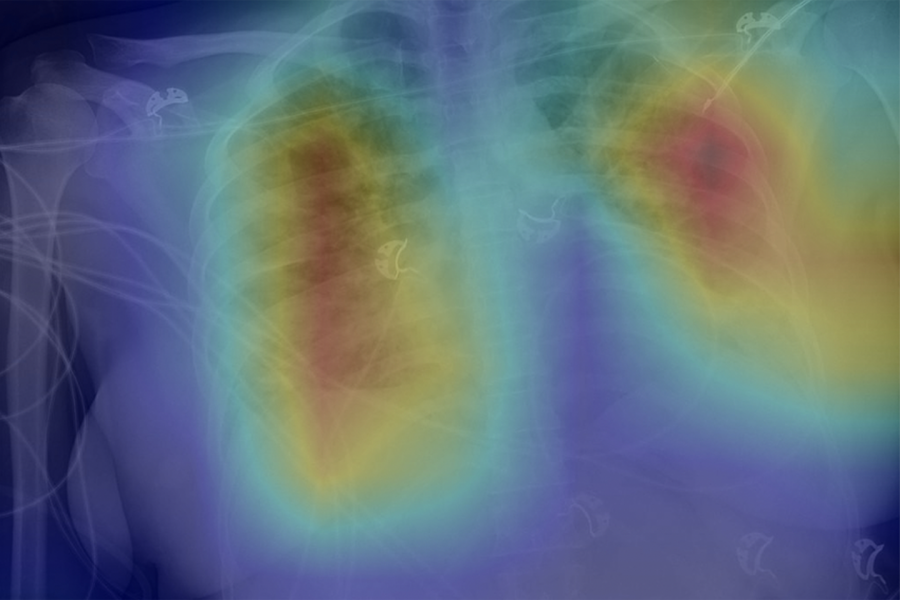

Covid chest x ray vs pneumonia. The primary findings of covid 19 on chest radiograph and ct are those of atypical pneumonia 40175 or organizing pneumonia 3234. The covid 19 virus can cause pneumonia a lung infection caused by viruses bacteria or fungal infections. If the patient with covid 19 takes a turn for the worse with new fevers respiratory deterioration and imaging on.

To target the issue at hand weve collected own datasetcombining the kaggle chest x ray dataset with the covid19 chest x ray dataset collected by dr. Based on recent studies cxr is not sensitive for the detection of covid 19 pneumonia. Given the diagnostic limitations of chest x ray cxr we believe lus may be a superior alternative for early covid 19 screening which is supported by our clinical experience and a review of available radiologic literature.

The differencet between pneumonia and covid 19 is usually determined clinically. Covid 19 pneumonia was more likely than non covid 19 pneumonia to have a peripheral distribution 80 vs 57 p 001 ground glass opacity 91 vs 68 p 001 fine reticular opacity 56 vs 22 p 001 vascular thickening 59 vs 22 p 001 and reverse halo sign 5 vs 1 p 005. Learn the warning signs who.

However imaging has limited sensitivity for covid 19 as up to 18 demonstrate normal chest radiographs or ct when mild or early in the disease course but this decreases to 3 in severe disease 8993. Pneumonia is a serious complication of the new coronavirus also known as covid 19. Treatment for covid.